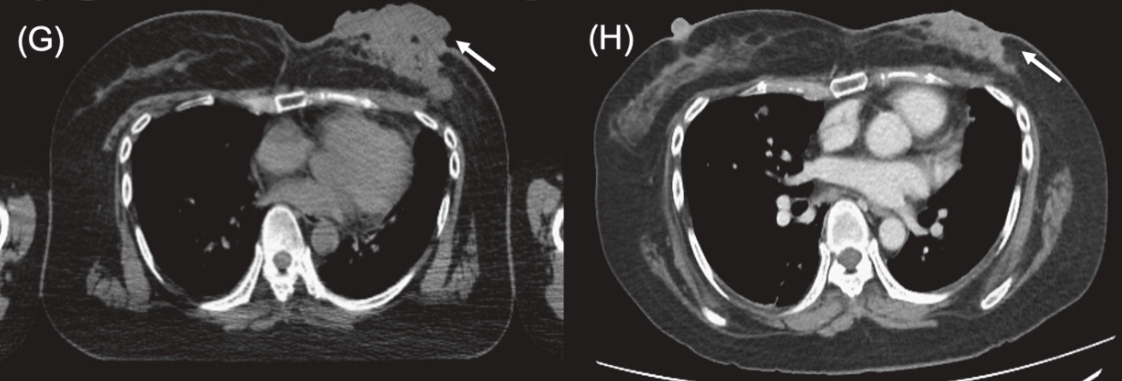

近期,一项发表于《Critical Reviews in Oncology/Hematology》的Meta分析,系统评估了硼中子俘获疗法(BNCT)治疗局部复发性头颈癌(LRHNC)的疗效与安全性。